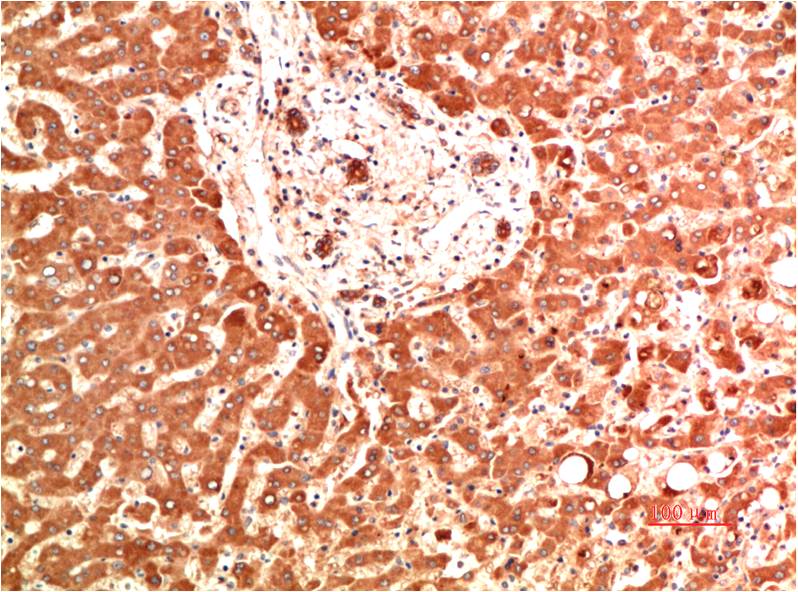

Collagen IV Mouse Monoclonal Antibody(5C9)

Catalog NO.:BE3725

Applications :IHC

Reactivity :H,R,M

Collagens are fibrous, extracellular matrix proteins with high tensile strength and are the major components of connective tissue, such as tendons and cartilage. All collagens contain a triple helix domain and frequently show lateral self-association in order to form complex connective tissues. Several collagens also play a role in cell adhesion, important for maintaining normal tissue architecture and function.

Recommended dilutions: IHC: 1:100-200

Specificity: The antibody can detects endogenous Collagen IV proteins.